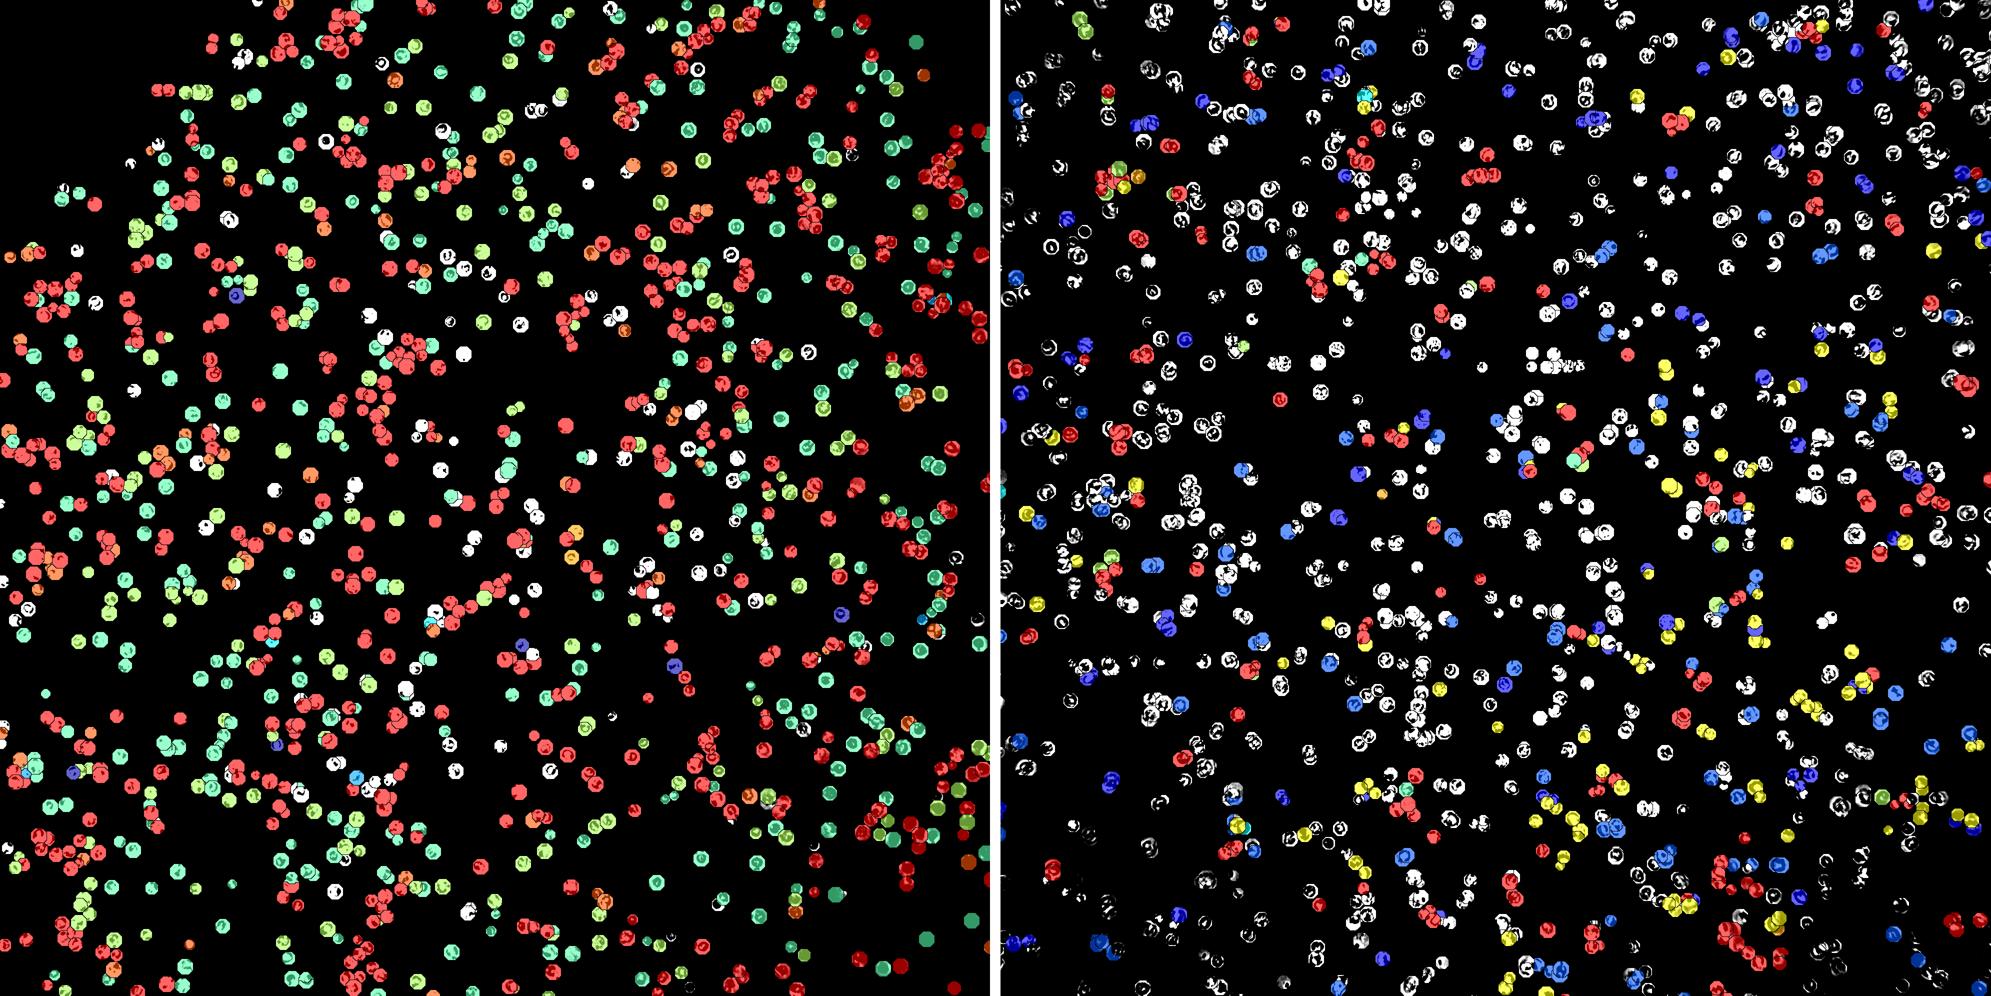

Cells labelled with CD15 CD8a

Peripheral blood lymphocytes

Inflammatory Disease

Cell populations before and after treatment